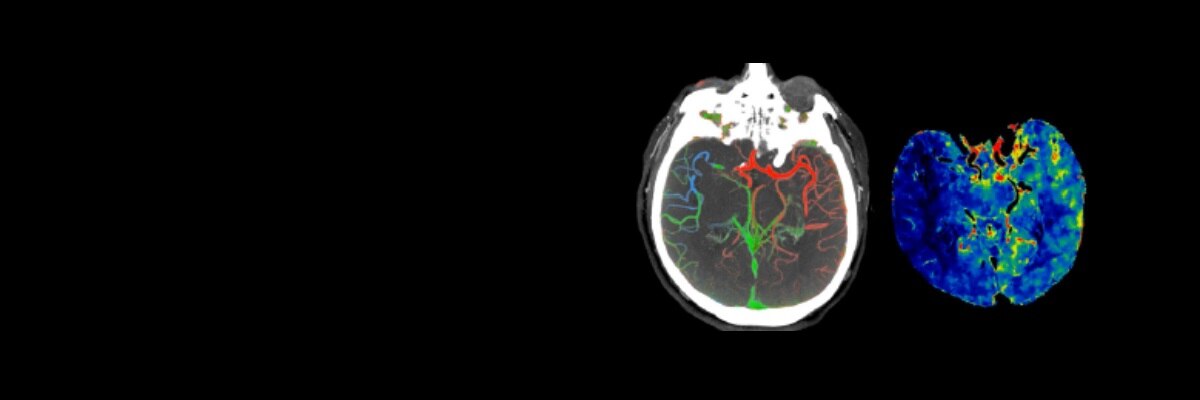

We help therapy innovators, researchers and healthcare providers accelerate how precision diagnostics and therapies are invented, made and used. Our products enable biological analysis, research, development and the manufacture of advanced therapies and vaccines. We also produce pharmaceutical diagnostics used in medical imaging.

• 3 patients are imaged every second using our pharmaceutical diagnostic agents